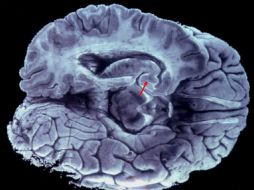

Tecnología Hemisferios cerebrales desconectados producirían doble personalidad 7 de mayo de 2017 - 09:26 hs Estudios científicos Ciencia médica

Suplementos Mito, que humanos usen sólo 10 por ciento del cerebro 23 de marzo de 2017 - 15:24 hs Calor de hogar Salud general